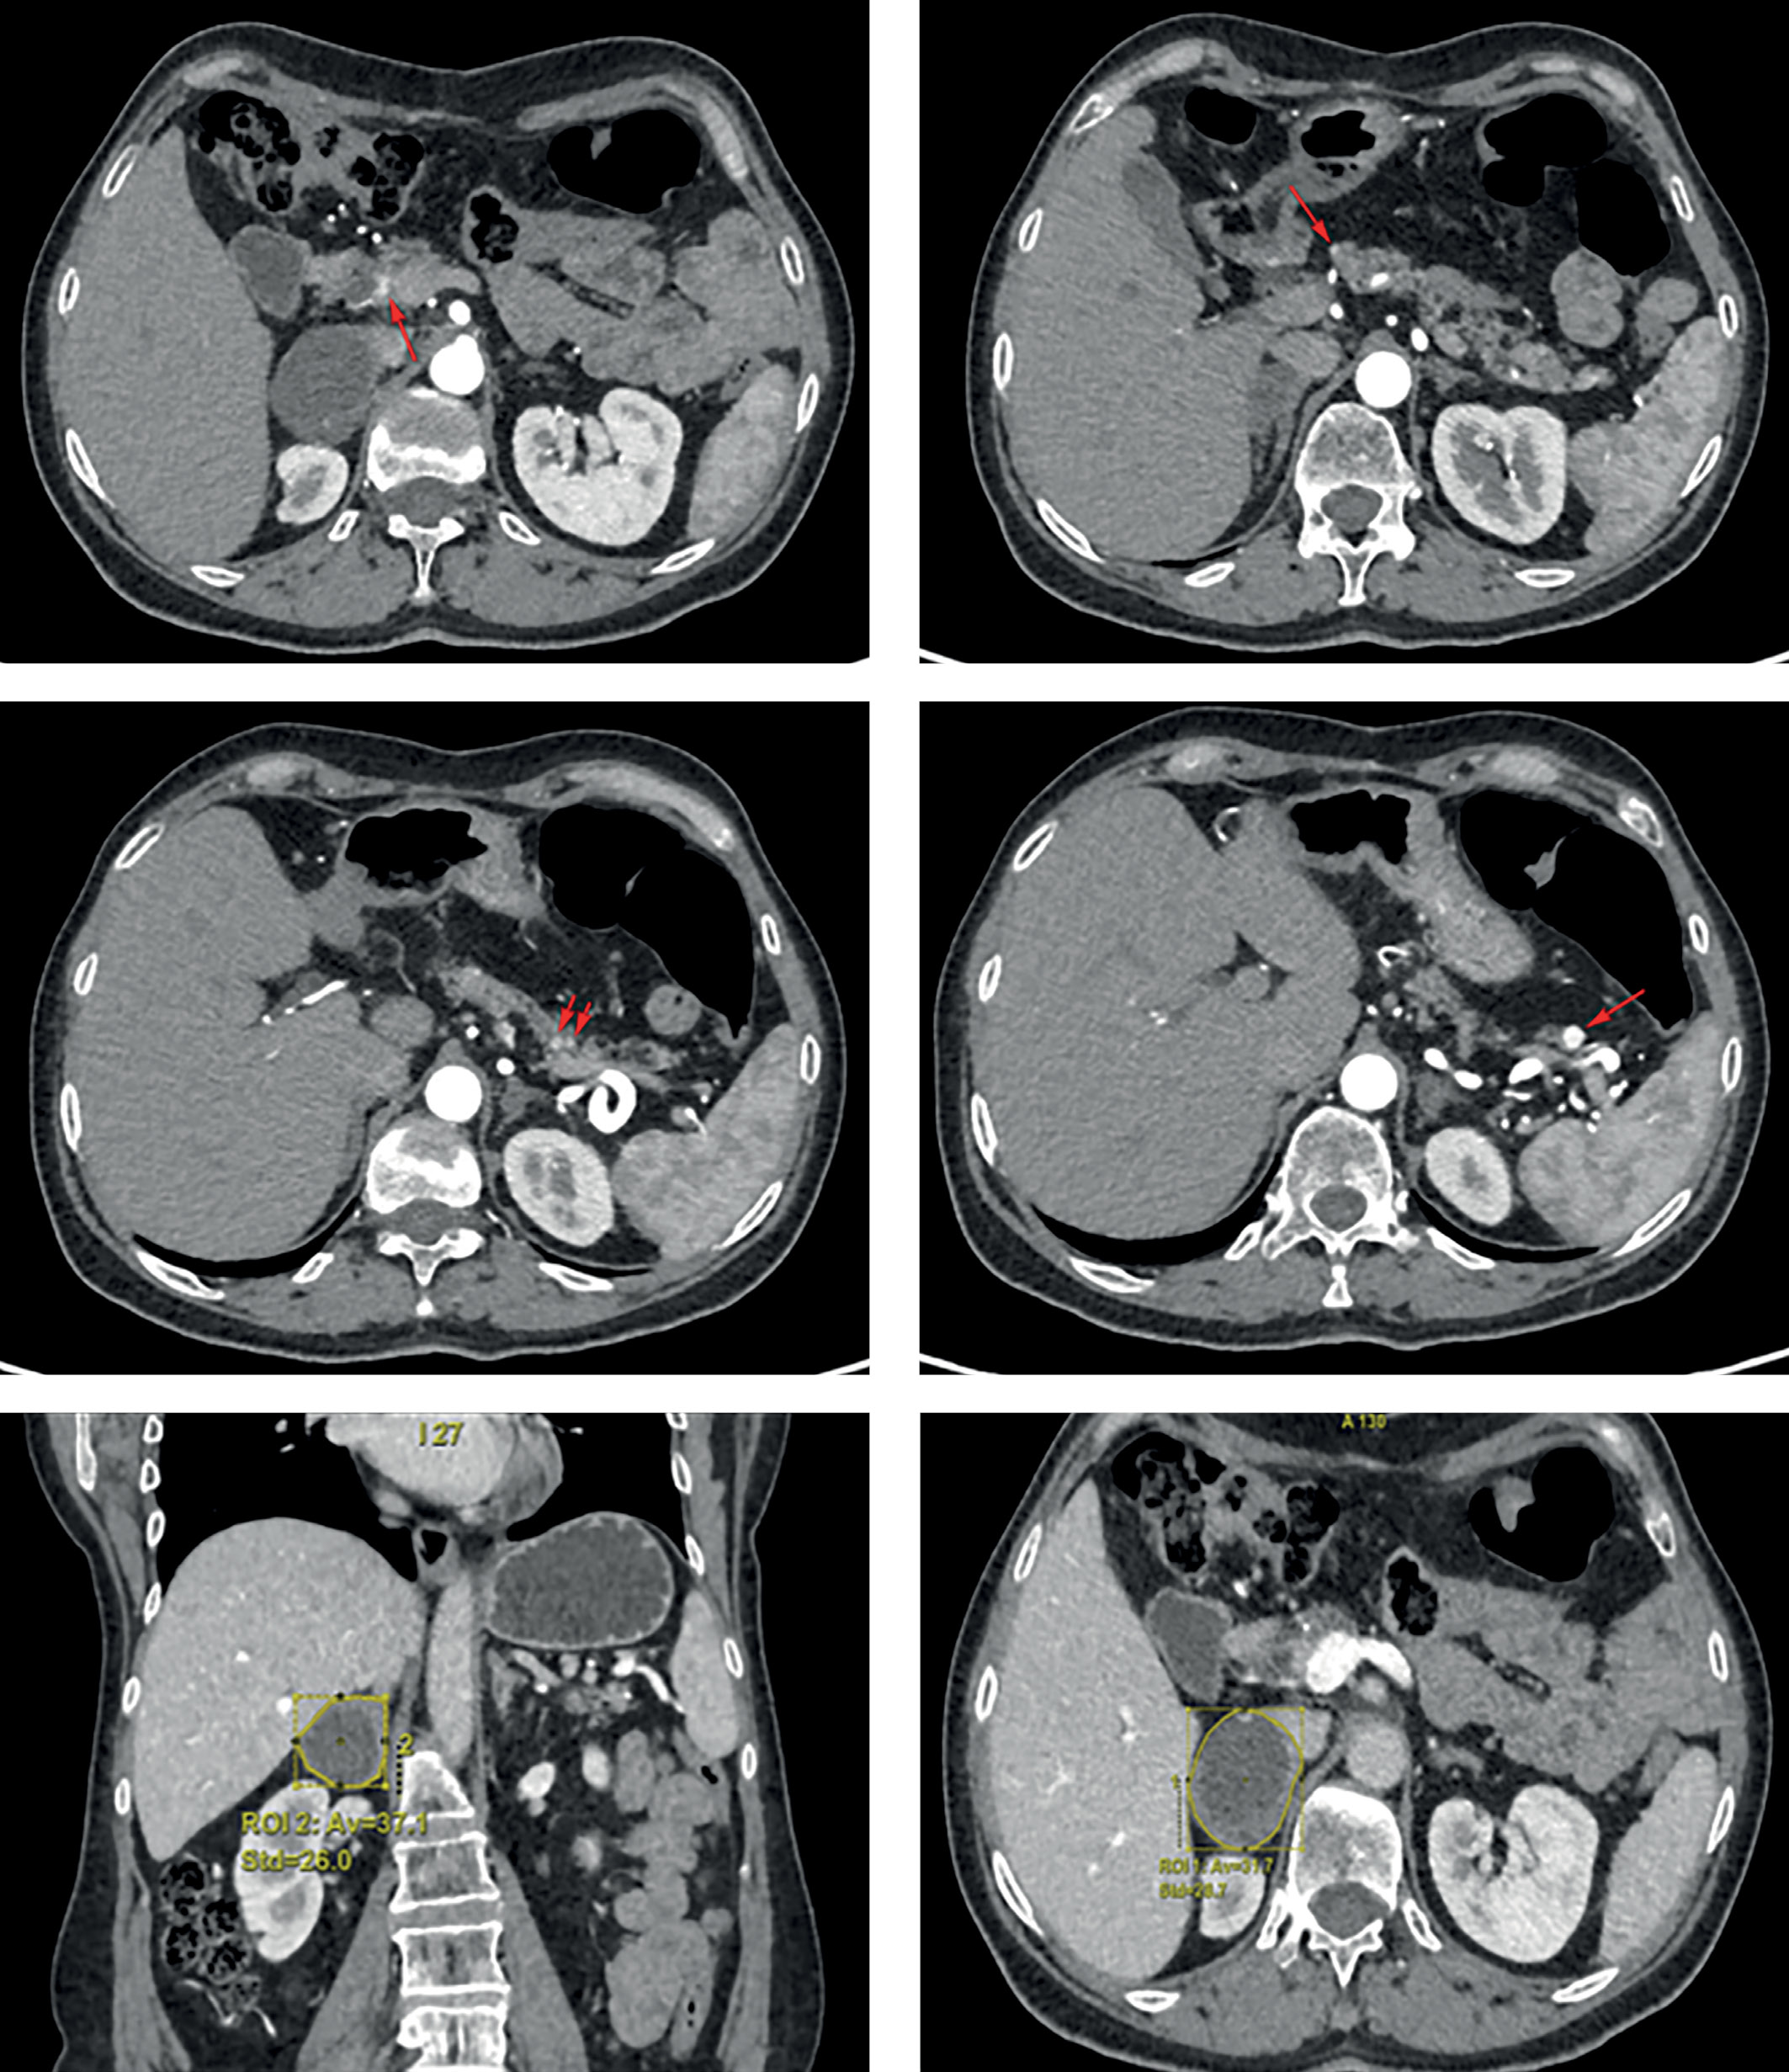

4. Рисунок 4. МСКТ органов брюшной полости. Красными стрелками отмечены образования ПЖ. Желтым контуром отмечено образование правого надпочечника. | |